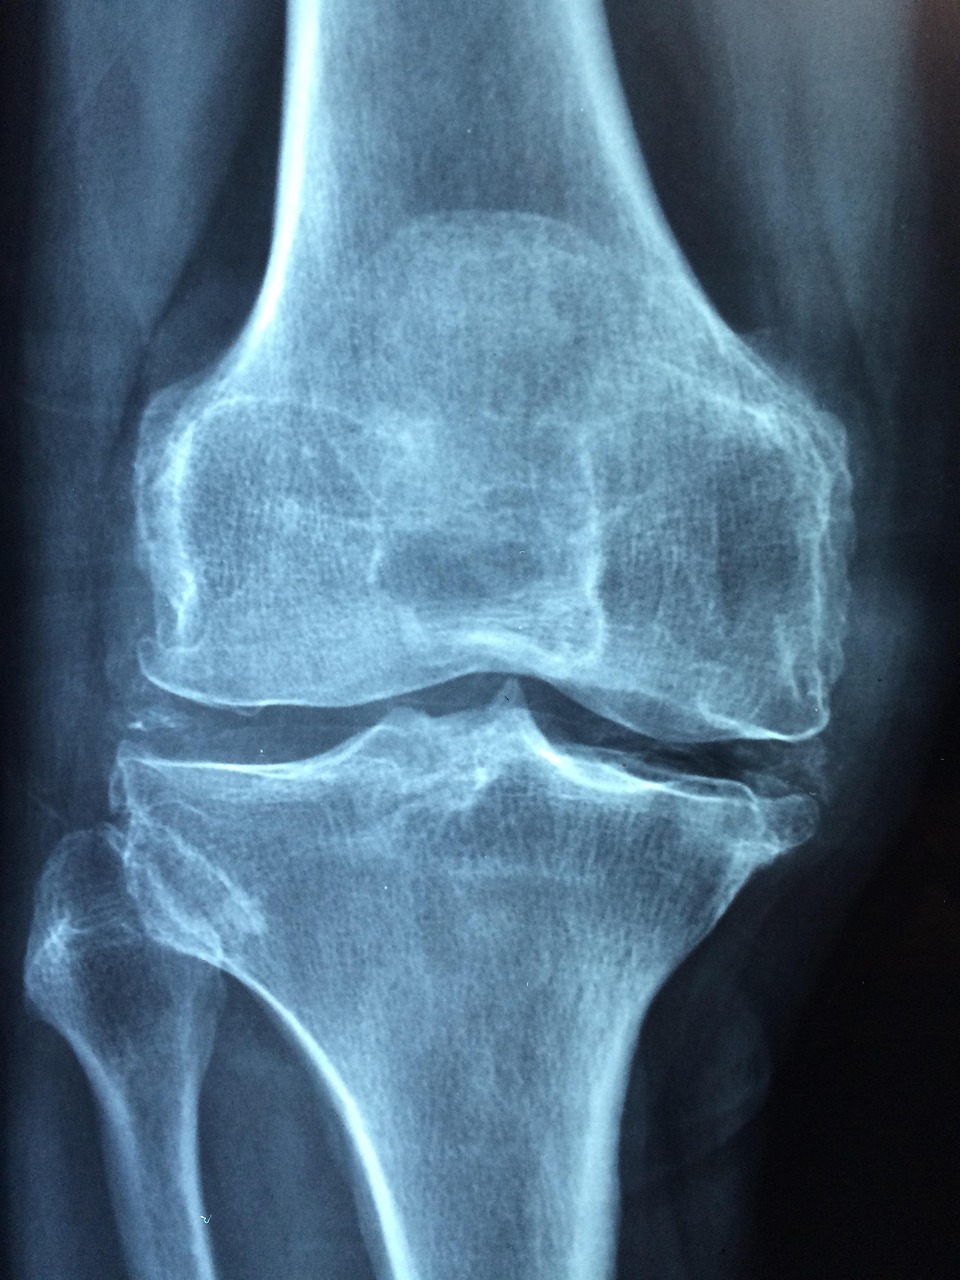

골다공증은 뼈의 강도가 약해져 작은 충격에도 골절이 쉽게 발생하는 질환으로, 특히 중장년층 이후부터 급격히 발병 위험이 커진다. 일반적으로 50대 여성과 60대 남성에게서 두드러지게 나타나며, 골밀도 감소 속도는 여성의 경우 폐경 이후 호르몬 변화로 인해 더 빨라진다. 많은 사람이 뼈 건강을 노화 과정의 자연스러운 일부로 생각하지만, 사실 골다공증은 예방할 수 있는 생활 습관 질환이다. 골다공증으로 인해 척추나 고관절에 골절이 생기면 회복 기간이 길어지고, 삶의 질이 급격히 저하된다. 따라서 중장년층이라면 지금부터라도 뼈 건강 관리에 집중해야 한다.

정기적인 건강검진과 골밀도 검사는 중장년층에게 필수적이다. 특히 가족력이 있거나 이미 골절 경험이 있는 경우에는 매년 골밀도 검사를 통해 조기 진단을 받는 것이 좋다. 필요하다면 전문의와 상담하여 맞춤형 영양제나 치료를 병행할 수 있다.

최근에는 골밀도 측정 장비가 발전하여 간단한 검사만으로도 자신의 뼈 상태를 정확히 파악할 수 있다. 이러한 전문적인 관리와 함께, 생활 속에서 꾸준히 자기 몸을 돌보는 자세가 장기적인 골다공증 예방의 핵심이다.